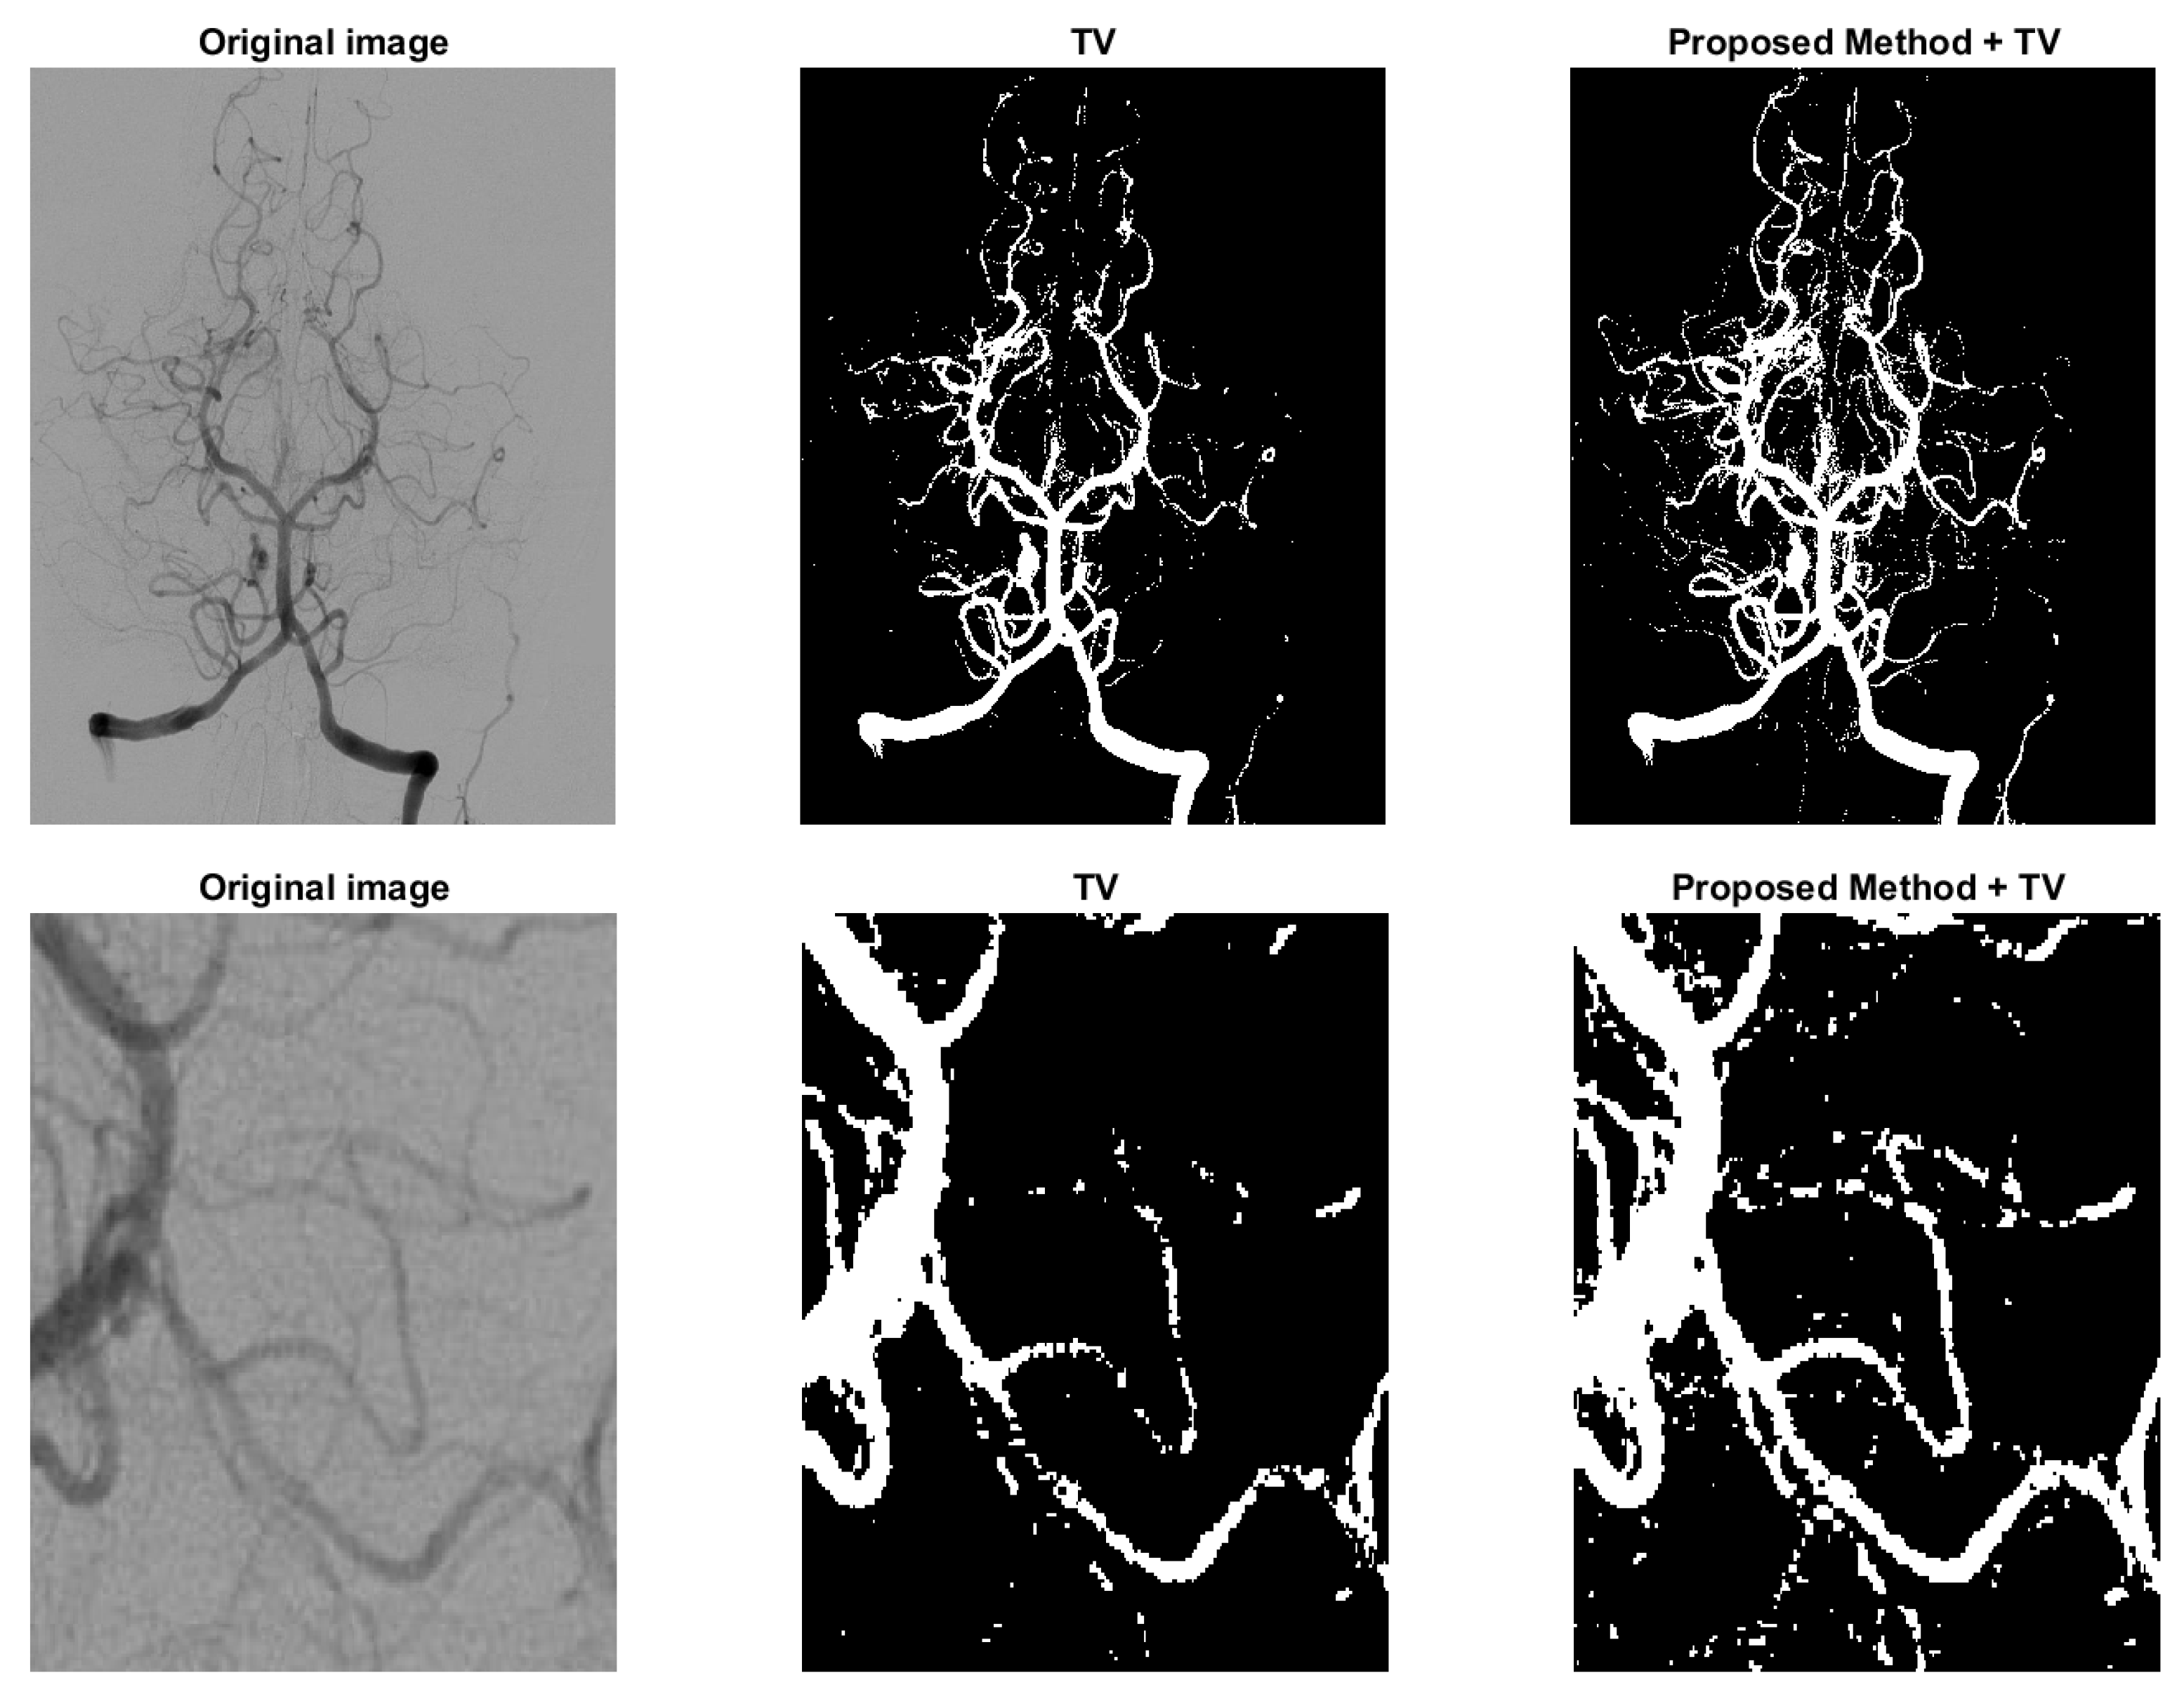

where and , f represents the image and and are the means of the foreground and background indicated by . Because in unsupervised method the parameter ’s are fixed, we just apply Gaussian kernel in the regularization added with TV. Since the added regularization term is smooth, the modified model can be solved with commonly used methods, such as ADMM. The proposed model (16) is compared with the one in [5] and some results are shown in Figure 8 and Figure 9. Figure 8 is a typical example of images with multi-scale features, the legs of the insect are long and slim, and some parts of the insect mix with the background due to low contrast. In variational models these parts with low contrast are naturally recognized as background. However, in the third figure of Figure 8, the legs are connected as a whole and some noise on the body caused by the texture pattern are removed. Another example is shown in Figure 9, which is human arteries. The image noise is strong and the contrast between the vessels and the background is very low. As shown in the second column of Figure 9, if the effect of TV is strong, the model will eliminate some fine structures together with noise. However, in the third column, the model retains some vessels, and we can find the corresponding parts from the original image in the first column. The parameters and in the Equation (16) should be fine-tuned. Typically, is between 0.01 to 1. should be as small as . Both results show the potential of the proposed regularization in enhancing segmentation of images with multi-scale structures and low contrast.

Figure 9.

Another example to show the effect of the proposed regularization on unsupervised model. Column 2: the model in [5] with TV regularization only. Column 3: the proposed model (16).